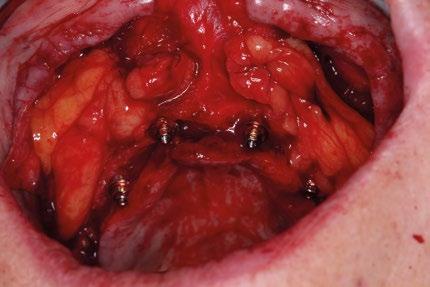

Procedimiento quirúrgico

Se levanta un colgajo de espesor total con incisiones vestibulares amplias. Se exponen las zonas de reborde alveo -

lar, tuberosidad y cuerpo cigomático. Se despega la membrana nasal bilateralmente para evitar perforaciones de esta y se coloca creos™ xenogain de Nobel Biocare, un material de injerto óseo hecho de hueso bovino purificado. Con ayuda de la guía, se realizan las perforaciones transnasales hasta alcanzar la cortical nasal, obteniendo estabilidad tricortical. Posteriormente, se retira la guía y se colocan los implantes.

Para los implantes cigomáticos NobelZygoma, se realiza osteotomía bicortical con fresas de bola y calibradas hasta alcanzar el cuerpo del cigoma. El implante se introduce con torque elevado, asegurando anclaje en la cortical cigomática. Los implantes pterigoideos se colocan posteriormente con angulación de 70–75° hacia la placa pterigoidea, favoreciendo estabilidad tricortical.

Uso de bolsas de Bichat

Se acceden mediante una pequeña incisión en la mucosa yugal y se disecan cuidadosamente para avanzar el tejido adiposo hacia el cuello de los implantes cigomáticos y parte de los cigomáticos, sirviendo como almohadilla biológica. Esta cobertura previene exposición y mejora la vascularización local. Antes de la sutura final, es cuando se rotan las bolsas de Bichat a través de pequeñas incisiones para cubrir los implantes.